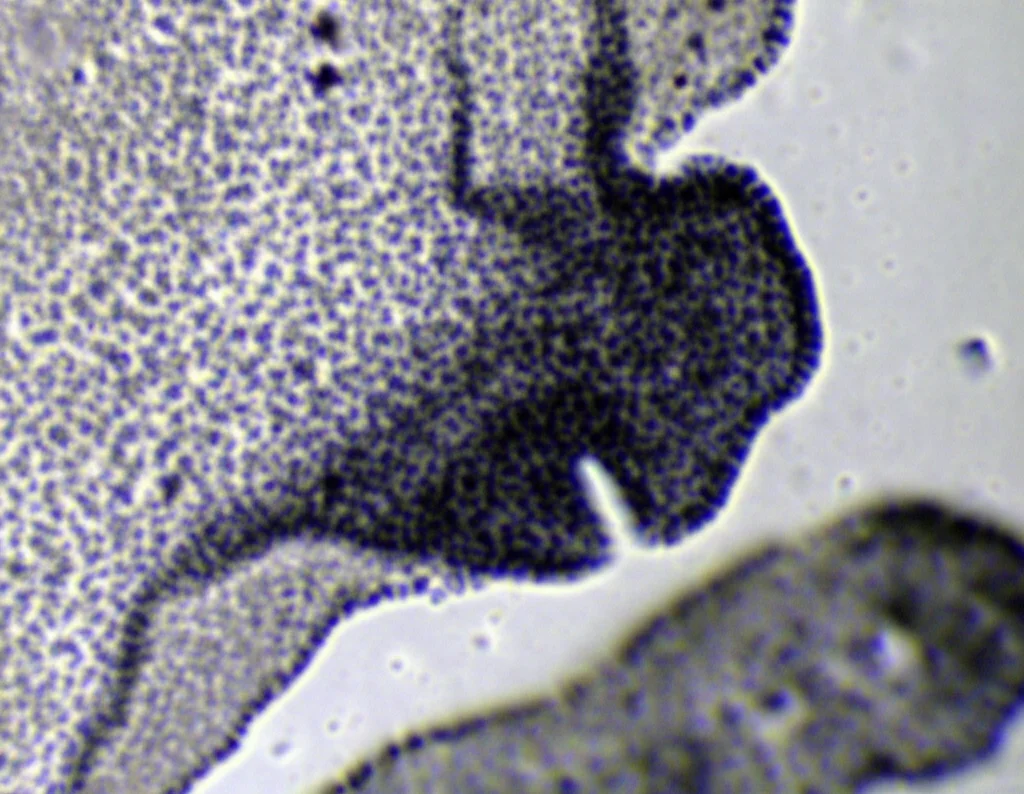

Qui le cose si fanno davvero interessanti. FGF10 è cruciale per la morfogenesi polmonare, in particolare per la corretta ramificazione delle vie aeree. Abbiamo preso dei polmoni embrionali di topo in uno stadio precoce (E11.25) e li abbiamo coltivati ex vivo (in laboratorio) con FGF10 normale o con i nostri FGF10-STAB.

I risultati sono stati sorprendenti:

- L’FGF10 wildtype (a 500 ng/ml) ha avuto effetti modesti.

- Gli FGF10-STAB (già a 100-200 ng/ml per STAB3 e STAB1/2 rispettivamente) hanno causato cambiamenti morfologici drastici: la ramificazione delle gemme epiteliali era soppressa, le gemme si dilatavano enormemente fino a formare strutture simili a cisti, e c’era un’espansione eccessiva del tessuto epiteliale distale (più cellule SOX9+ e E-caderina+) a scapito di quello prossimale (meno cellule SOX2+ e αSMA+).

In pratica, l’FGF10 super-stabile mandava un segnale troppo forte e persistente, sbilanciando il delicato equilibrio tra proliferazione, differenziazione e ramificazione necessario per formare un polmone normale. Sembrava proprio un caso di segnalazione ectopica: il segnale arrivava dove non doveva o durava troppo a lungo.